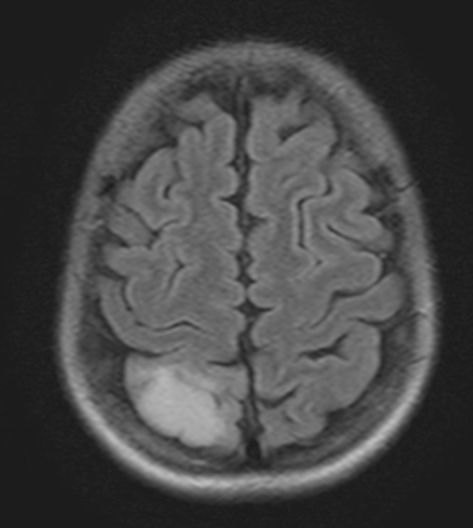

МРТ головного мозга -очаг ишемии в ПСМА с отёком 29х20 мм

• не типичный очаг для ПСМА

• откуда отек?

• а нет ли здесь венозного инсульта?

Диск был пересмотрен рентгенологами. И да, это не инсульт в ПСМА

Итак, на МРТ не инсульт, а опухоль, у пациентки не повторные инсульты, а эпилепсия, фокальная форма